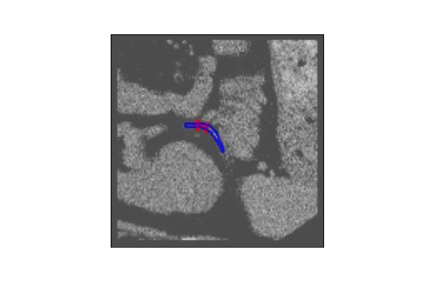

The human annotations are imperfect, especially when produced by junior practitioners. Multi-expert consensus is usually regarded as golden standard, while this annotation protocol is too expensive to implement in many real-world projects. In this study, we propose a method to refine human annotation, named Neural Annotation Refinement (NeAR). It is based on a learnable implicit function, which decodes a latent vector into represented shape. By integrating the appearance as an input of implicit functions, the appearance-aware NeAR fixes the annotation artefacts. Our method is demonstrated on the application of adrenal gland analysis. We first show that the NeAR can repair distorted golden standards on a public adrenal gland segmentation dataset. Besides, we develop a new Adrenal gLand ANalysis (ALAN) dataset with the proposed NeAR, where each case consists of a 3D shape of adrenal gland and its diagnosis label (normal vs. abnormal) assigned by experts. We show that models trained on the shapes repaired by the NeAR can diagnose adrenal glands better than the original ones. The ALAN dataset will be open-source, with 1,594 shapes for adrenal gland diagnosis, which serves as a new benchmark for medical shape analysis. Code and dataset are available at https://github.com/M3DV/NeAR.